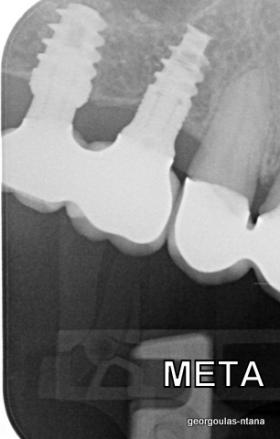

Ο ασθενής  προσήλθε στο ιατρείο μας θέλοντας να βελτιώσει την εμφάνιση των πρόσθιων δοντιών του και να αποκαταστήσει την υγεία κ την λειτουργία όλου του στόματος. Πραγματοποιήθηκε περιοδοντική θεραπεία κ ενδοδοντικές θεραπείες (απονευρώσεις) όπου κρίθηκε απαραίτητο και στη συνέχεια τοποθετήθηκαν 3 εμφυτεύματα, 2 δεξιά στις θέσεις του πρώτου κ δεύτερου γομφίου κ 1 αριστερά στη θέση του πρώτου προγομφίου. Κατά την  τοποθέτηση των 2 εμφυτευμάτων της δεξιάς πλευράς, πραγματοποιήθηκε κλειστή ανύψωση ιγμορείου με το σύστημα Piezotome-Intralift , τεχνική που εξασφαλίζει τη μικρότερη δυνατή επέμβαση κ τη μικρότερη μετεγχειρητική ταλαιπωρία (minimally invasive), καθώς κ αυξητικους παράγοντες PRF. Σε όλη τη διάρκεια της θεραπείας  ο ασθενής ήταν καλυμμένος τόσο αισθητικά όσο και λειτουργικά με προσωρινές μεταβατικές αποκαταστάσεις. 4 μήνες μετά την  τοποθέτηση των εμφυτευμάτων κ την οστεοενσωμάτωσή τους, ακολούθησε η τοποθέτηση των μόνιμων αποκαταστάσεων.